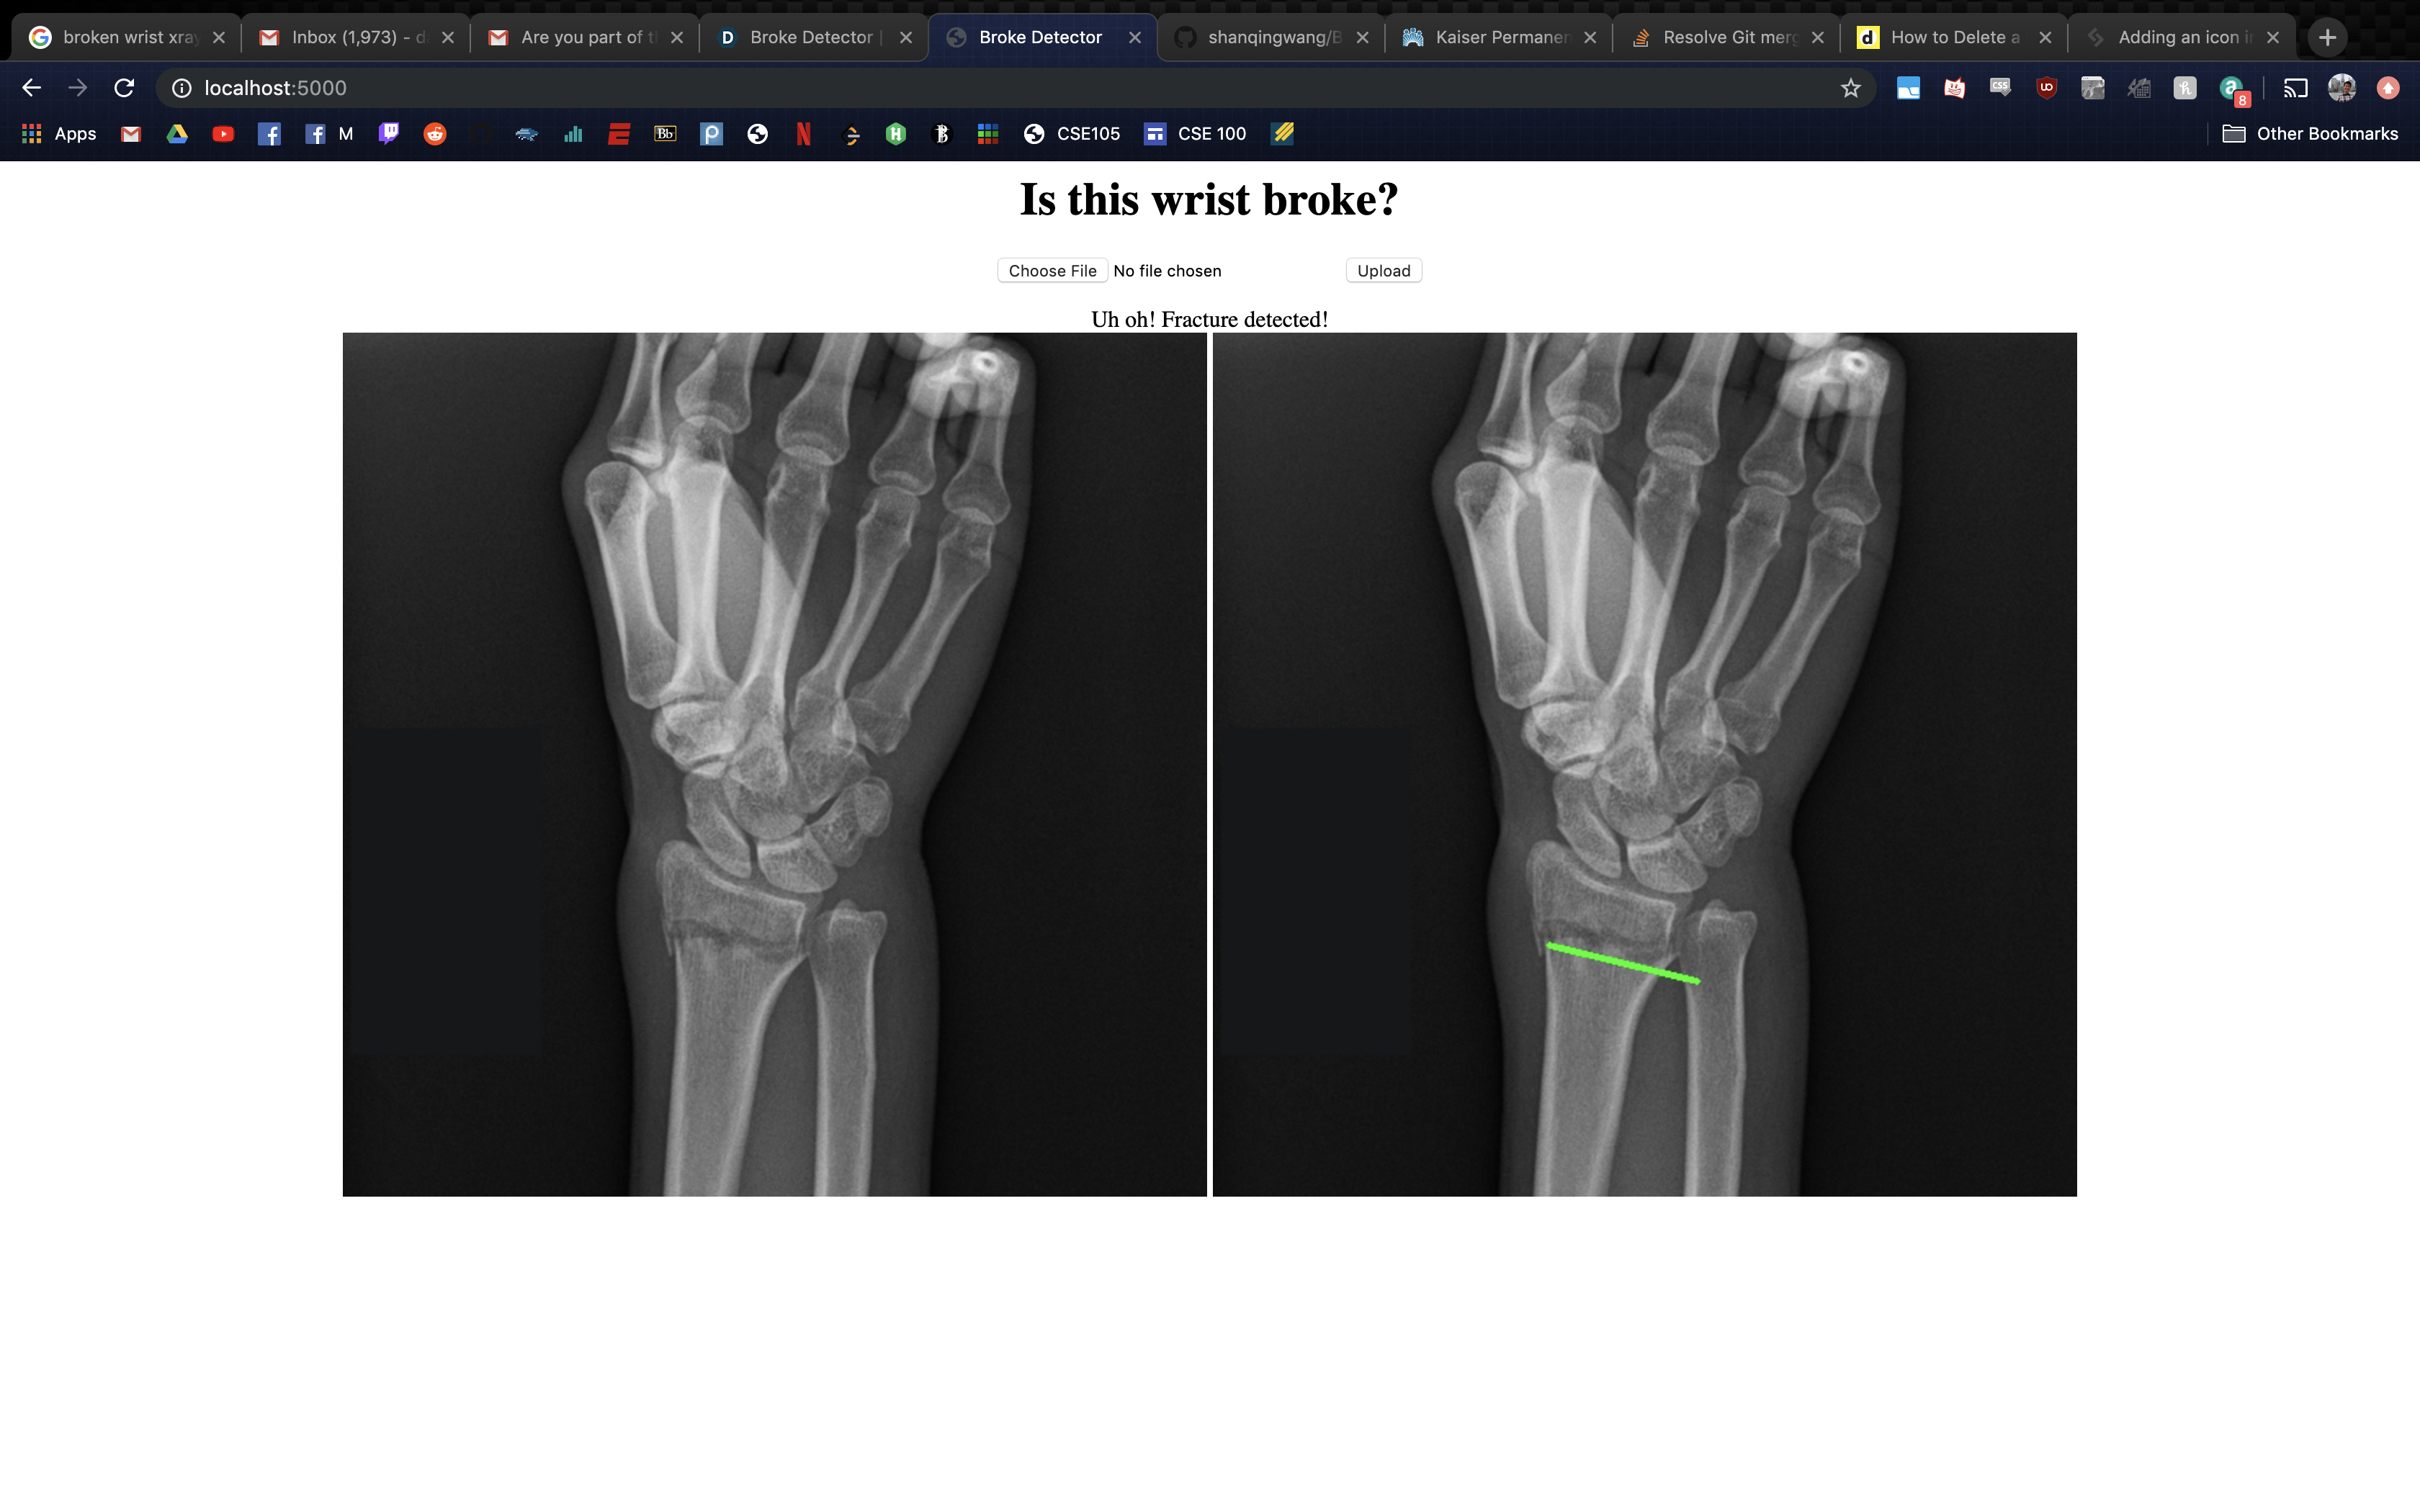

Broke Detector is a simple tool to help analyze the site of wrist injury. It helps doctors decide a) whether the bones are broken or not (which is admittedly very simple for humans, but not for computers) and b) provides tools such as a protractor to provide an objective measurement of how misaligned bones are. Broke Detector aims not to replace the orthopedist, but to aid them.

The actual detection algorithm is the guts of this project (no machine learning involved). The process is as follows: Thresholding: Reasons for this will be listed in the next section, we did this using color histograms to determine the percentile of certain pixel values. Edge detection: We used a simple Söbel kernel (however, not the default opencv one) to handle edge detection, as it was simple to detect only horizontal edges. Hough transform: This is the guts of the algorithm, which decides where horizontal lines are in the X-Ray. It sounds dumb, but choosing the lowest isolated horizontal line almost always results in finding the break in the bone. Flask: We developed a locally hosted web application which supports uploading from the computer. The HTML formatted site displays the results of the Python calculations.

While we were very passionate about doing something involving the X-rays, there were a couple issues with our process. The common state-of-the-art solutions to a problem like this would be stuffing a bunch of data into a faster R-CNN and let it handle the detection. However, we lacked both the volume and consistency of data to make this a reality: many of the research papers that tackled this problem partnered with a medical office, which would provide them a lot of consistent and annotated images to work with. Because of the hodgepodge of different variables that differ with each image we ripped off of Google images, we had to use techniques like color thresholding, as the brightness of what was bone and what was background differed from image to image. Even now, the algorithm isn't quite perfect. It still struggles to detect fractures that are close to the end of the radius/ulna.